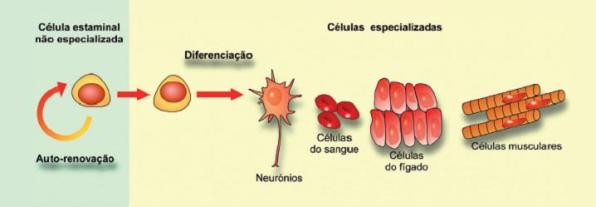

As células estaminais (CE) distinguem-se das restantes células do organismo por apresentarem três propriedades fundamentais: são células indiferenciadas e não especializadas; têm a capacidade de se auto-renovar e dividir indefinidamente e são capazes de se diferenciar em linhagens celulares distintas (Figura 1).

Durante o desenvolvimento embrionário, estas células especializam-se, originando os vários tipos de células do corpo, desde as células do músculo cardíaco, células nervosas, glóbulos vermelhos ou células da pele. Mais tarde, no indivíduo adulto, as CE reparam tecidos danificados e substituem as células que vão sendo destruídas.

Figura 1 – Propriedades das células estaminais.

Com o intuito de esclarecer a capacidade de diferenciação das CE em diversos tipos de células especializadas, estas foram classificadas em 4 graus ou níveis de diferenciação:

- Totipotentes – Células estaminais com capacidade de diferenciação em qualquer tipo de tecido embrionário e extraembrionário.

- Pluripotentes – Descendentes diretos das células totipotentes com capacidade de diferenciação nos três folhetos embrionários que constituem a matriz embrionária de todas as células do corpo. Todos os tipos de células especializadas que constituem o corpo humano são provenientes destas células.

- Multipotentes – Possuem a capacidade de auto-renovação e formação de múltiplos tipos celulares diferenciados, mas restritos a um determinado órgão ou sistema fisiológico. A sua função é a manutenção do nível de células maduras, sendo as peças fundamentais na regeneração de tecidos danificados ou doentes.

- Unipotentes – Originam somente um tipo de célula, mas, ao contrário das células não estaminais, são auto-renováveis.